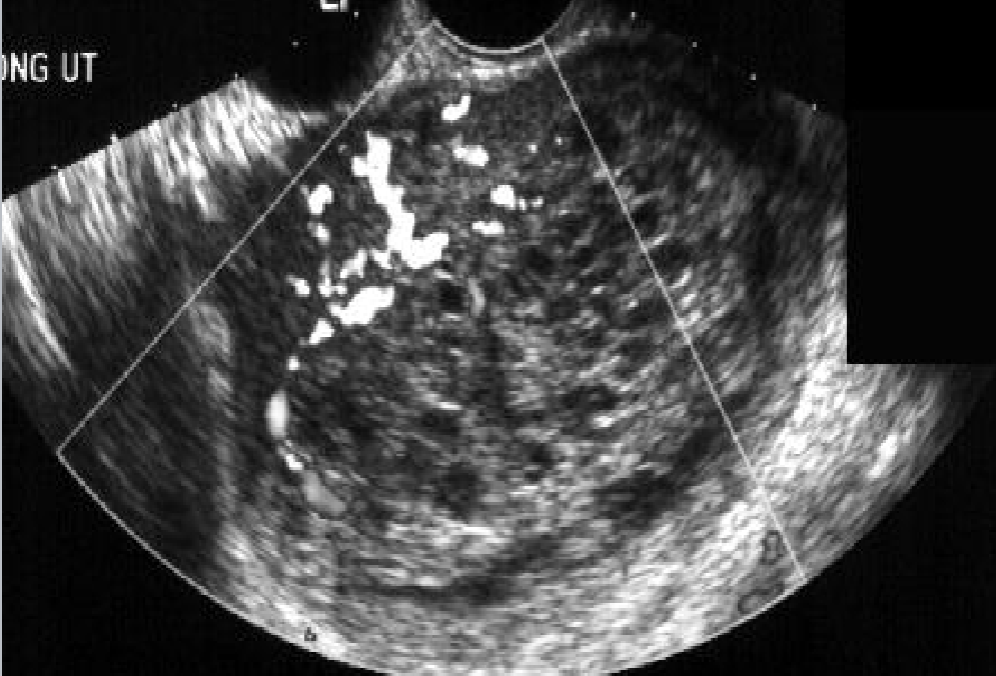

Theca Lutein Cysts

Bilateral

contain multiple cysts + septa

Largest when hCG production at greatest

12 - 24 weeks GA

Have potential to twist and hemorrhage, causing areas of solid echogenicity within cyst